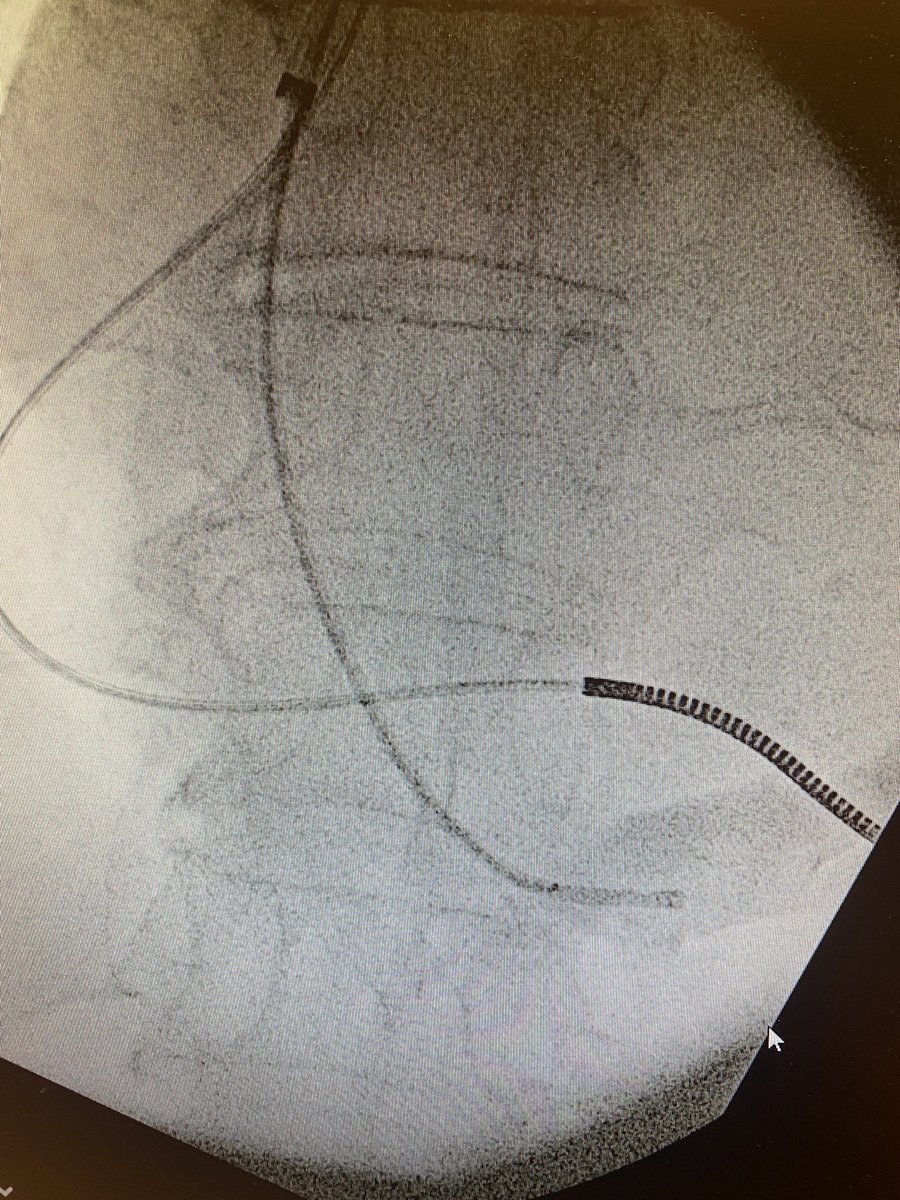

Images from the previous case

Right sided CRT upgrade in patient with laminopathy and huge (10x10cm) right atrium. Easy CS cannulation with Worley sheath + handshaped Cordis MPB 1 guide and then amplatz wire for stability during PL lead placement - thank you @seth_j_worley for tips!